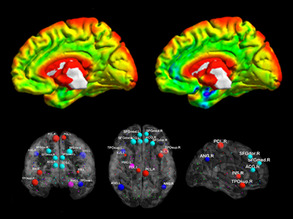

Mind and Matter